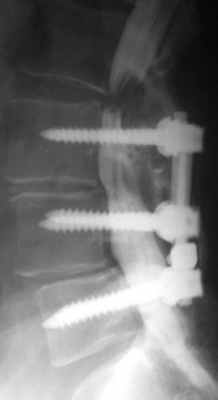

Послеоперационная нестабильность позвоночника обычно наступает после больший объемных операций (ламинэктомия), сопровождаемых резекцией суставных отростков. Эти состояния, как правило, сопровождаются сильным болевым синдромом, как вертеброгенным, так и корешковым.

![]()

Нестабильность после декомпрессивной ламинэктомии. Рентгенография и МРТ позвоночника в сагиттальной и аксиальной плоскостях. Ламинэктомия на нескольких уровнях, постламинэктомический спондилолистез и дефект дуг.